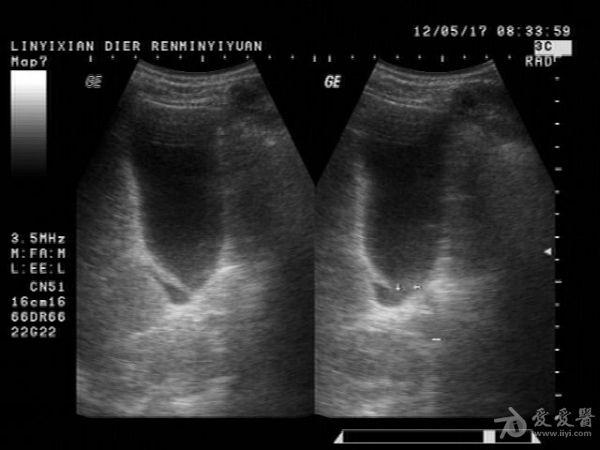

邹褶吧,不是憩室

很明显的胆囊皱褶,这种现象应该很常见的,肝硬化的时候胆囊比正常要大些

应该是胆囊皱褶。